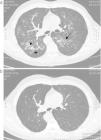

Pulmonary toxicity by riluzole

Toxicidad pulmonar por riluzole